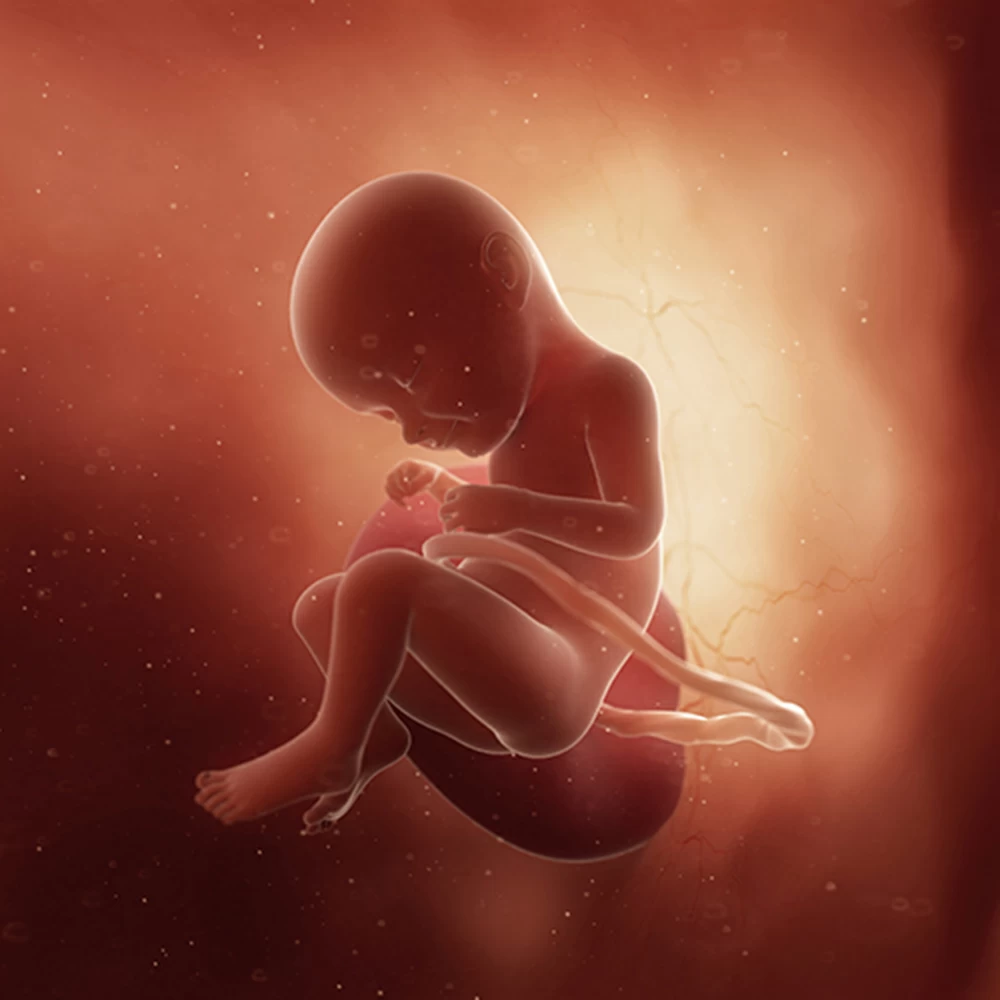

Неделя № 30

Масса тела увеличивается до 1300-1350 грамм, рост остается примерно тем же – около 38-39 см.

Постоянно накапливается подкожная жировая клетчатка, расправляются кожные складки. Ребенок приспосабливается к недостатку места и принимает определенное положение: сворачивается, руки и ноги скрещиваются.